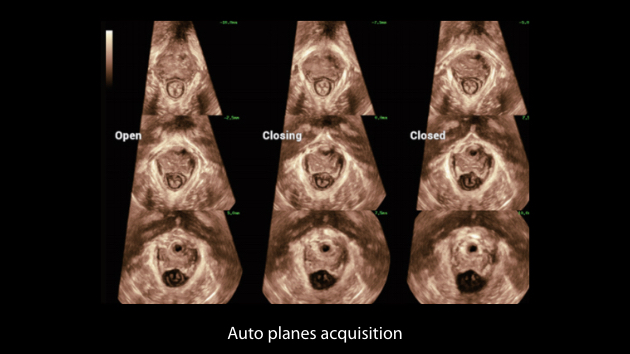

Intelligenza completa orientata allo scenario clinico

L'innovativa soluzione Smart Scene 3D consente l'identificazione automatica delle caratteristiche dei tessuti e fornisce una diagnosi specifica per i diversi distretti di esame durante l'intera procedura. Questa innovazione aumenta lŌĆÖaccuratezza e la sicurezza diagnostica, migliorando lŌĆÖefficienza.